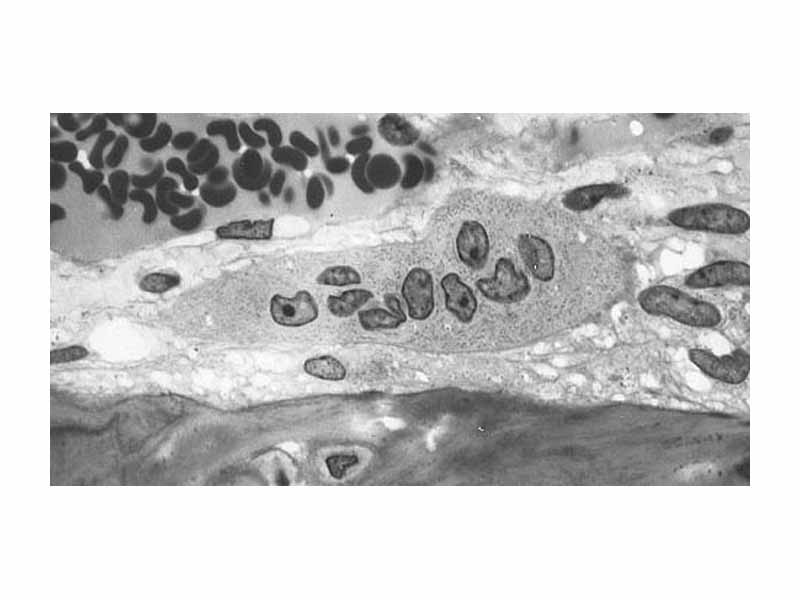

Osteoclast displaying many nuclei within its foamy cytoplasm